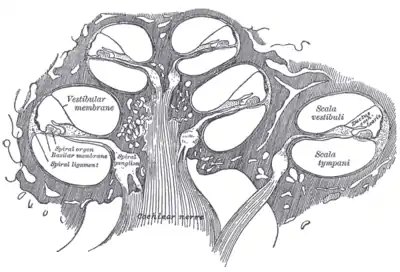

Cross section of the cochlea | |

- Three scalae or chambers:

- the vestibular duct or scala vestibuli (containing perilymph), which lies superior to the cochlear duct and abuts the oval window

- the tympanic duct or scala tympani (containing perilymph), which lies inferior to the cochlear duct and terminates at the round window

- the cochlear duct or scala media (containing endolymph) a region of high potassium ion concentration that the stereocilia of the hair cells project into

- Reissner's membrane, which separates the vestibular duct from the cochlear duct

- The osseous spiral lamina, a main structural element that separates the cochlear duct from the tympanic duct

- The basilar membrane, a main structural element that separates the cochlear duct from the tympanic duct and determines the mechanical wave propagation properties of the cochlear partition

- The Organ of Corti, the sensory epithelium, a cellular layer on the basilar membrane, in which sensory hair cells are powered by the potential difference between the perilymph and the endolymph

- hair cells, sensory cells in the Organ of Corti, topped with hair-like structures called stereocilia

The walls of the hollow cochlea are made of bone, with a thin, delicate lining of epithelial tissue. This coiled tube is divided through most of its length by an inner membranous partition. Two fluid-filled outer spaces (ducts or scalae) are formed by this dividing membrane. At the top of the snailshell-like coiling tubes, there is a reversal of the direction of the fluid, thus changing the vestibular duct to the tympanic duct. This area is called the helicotrema. This continuation at the helicotrema allows fluid being pushed into the vestibular duct by the oval window to move back out via movement in the tympanic duct and deflection of the round window; since the fluid is nearly incompressible and the bony walls are rigid, it is essential for the conserved fluid volume to exit somewhere.

The lengthwise partition that divides most of the cochlea is itself a fluid-filled tube, the third 'duct'. This central column is called the cochlear duct. Its fluid, endolymph, also contains electrolytes and proteins, but is chemically quite different from perilymph. Whereas the perilymph is rich in sodium ions, the endolymph is rich in potassium ions, which produces an ionic, electrical potential.

The hair cells are arranged in four rows in the Organ of Corti along the entire length of the cochlear coil. Three rows consist of outer hair cells (OHCs) and one row consists of inner hair cells (IHCs). The inner hair cells provide the main neural output of the cochlea. The outer hair cells, instead, mainly 'receive' neural input from the brain, which influences their motility as part of the cochlea's mechanical "pre-amplifier". The input to the OHC is from the olivary body via the medial olivocochlear bundle.

The cochlear duct is almost as complex on its own as the ear itself. The cochlear duct is bounded on three sides by the basilar membrane, the stria vascularis, and Reissner's membrane. The stria vascularis is a rich bed of capillaries and secretory cells; Reissner's membrane is a thin membrane that separates endolymph from perilymph; and the basilar membrane is a mechanically somewhat stiff membrane, supporting the receptor organ for hearing, the Organ of Corti, and determines the mechanical wave propagation properties of the cochlear system.

The cochlea and vestibule, viewed from above. Cross-section of the cochlea.

Cross-section of the cochlea.